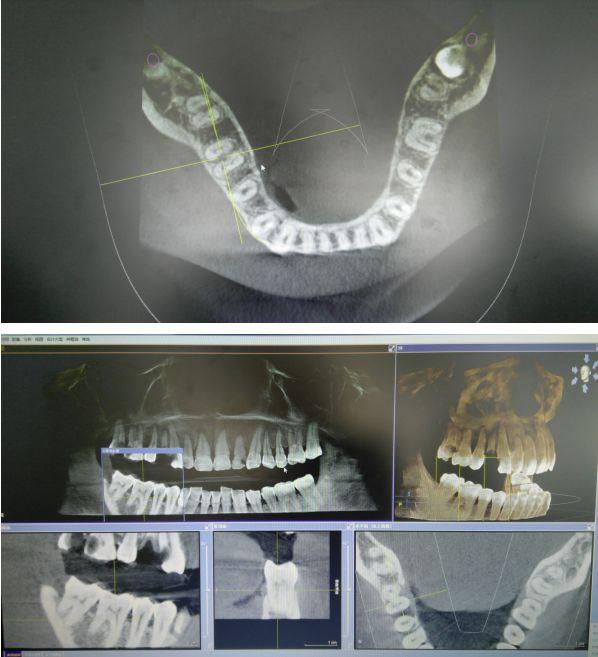

CBCT掃描可準確分析頜骨植入?yún)^(qū)的骨質(zhì)、骨量、骨密度及植體與下頜神經(jīng)管、上頜竇的關(guān)系,臨床醫(yī)生可以在圖像上模擬種植,直接與患者進行溝通及交流,并可指導手術(shù)者在手術(shù)方案中避開危險區(qū)域,手術(shù)的性。此外,臨床醫(yī)生還可以利用CT數(shù)據(jù)進行數(shù)字模型重建,配合軟件預(yù)先做好手術(shù)模板使種植手術(shù)更快捷。